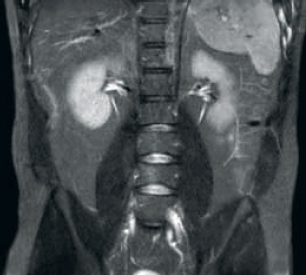

Result: Improved SNR and image resolution

Result: Noisy images using identical scan parameters

Increased consistency and enhanced image quality dStream RF receive technology digitizes the MR signal directly in the RF coil, resulting in an increase of up to 40% more SNR* throughout the whole image volume. Simplified workflow and improved throughput Posterior coil integrated into the tabletop eliminates coil handling in 60% of exams. Lightweight conforming anterior coils and singlehanded, single cable coil connections add to operational ease.